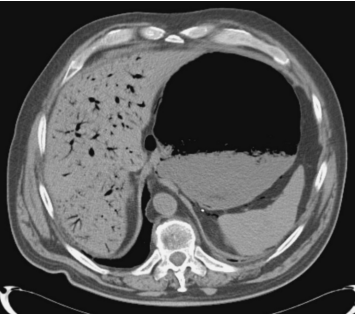

Assinale a alternativa que apresenta o achado da tomografia computadorizada acima.